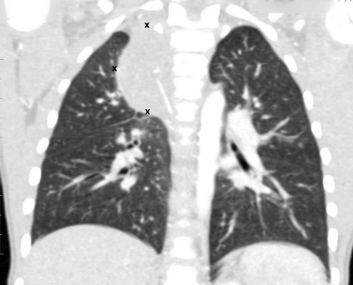

КТ органов грудной клетки при туберкулезе

Очаговые изменения на КТ легких, подозрительные на туберкулезное поражение (выделено красным)

Туберкулез поражает пациентов любого возраста и пола, легкие вовлекаются в процесс наиболее часто. Болезнь считают социально опасной, так как при несвоевременной диагностике открытой формы (выделение микобактерий в окружающую среду при кашле) высок риск инфицирования окружающих людей. КТ органов грудной клетки при туберкулезе назначают в следующих ситуациях: